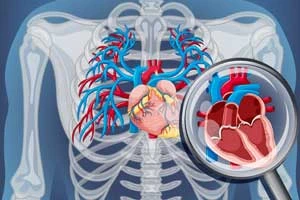

Open Heart Surgery

Comprehensive surgical procedures for complex heart conditions

Open Heart Surgery

Comprehensive surgical procedures for complex heart conditions